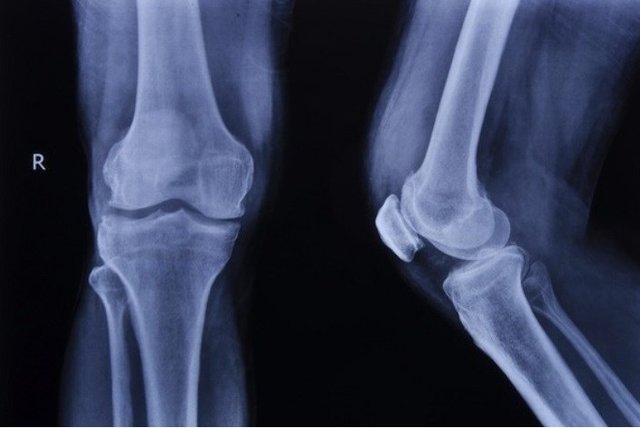

سهمانی، ساخت این داربست را با استفاده از چاپگرهای سهبعدی و از ترکیب و سنتز بایوسرامیک (بردیجیت) و نانوذرات مغناطیسی (مگنتیت) دانست و ادامه داد: نتایج به دست آمده نشان داد که داربست تولید شده زیست سازگار بوده و خواص بیولوژیکی و مکانیکی مشابه با استخوان طبیعی دارد و از تخلخل لازم برای رشد سلولهای استخوانی جهت ترمیم و بازسازی یک بخش صدمه دیده استخوان برخودار است.

مجری طرح با اشاره به کاربردهای داربست تولید شده، خاطر نشان کرد: از این داربست میتوان در بخش مهندسی پزشکی، جهت ترمیم و بازسازی بخشهای صدمه دیده استخوان بهره گرفت. از طرفی به دلیل دارا بودن نانوذرات مغناطیسی (مگنتیت) این قابلیت را دارد که با قرار گرفتن در یک میدان مغناطیسی AC، گرما تولید کند و سبب افزایش درجه حرارت بافت اطراف خود شود.